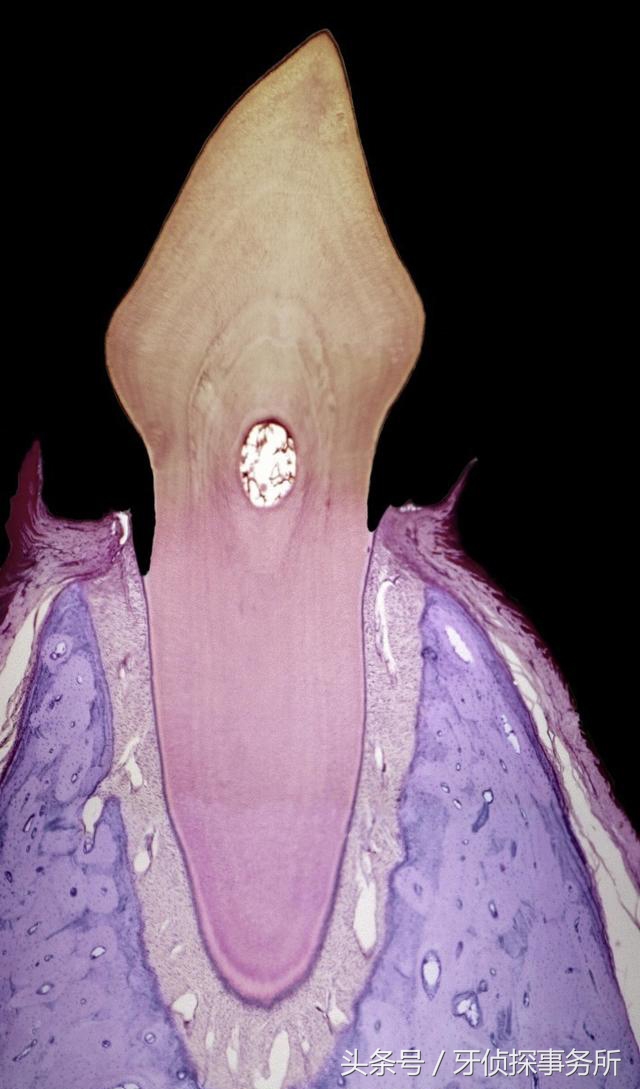

患上牙周病的人会发觉自己的牙齿越长越长,不要惊奇的以为牙齿逆生长了,那是牙龈牙槽骨正在不断萎缩,也就是你牙齿的根基变浅了,牙根暴露出来了,牙齿松动不稳固了,随时有掉牙的风险。

这是一个漫长潜伏的过程:聚集于牙垢、牙菌斑、牙石“温床”上而孳生的细菌,分解食物残渣,释放毒素。牙龈最容易受到细菌毒素的侵蚀,产生炎症,并逐渐蔓延到牙根、牙槽骨。细菌在牙槽骨中生长繁殖,新陈代谢,破坏毛细血管,阻断营养供给,降低成骨细胞活性,最终导致牙槽骨萎缩、骨质流失,牙床降低、牙齿根基变浅、牙齿变长。

小树因水土流失,树根暴露会倒塌;牙齿如果因牙周组织逐渐萎缩,牙根渐渐暴露,自然会松动而脱落。